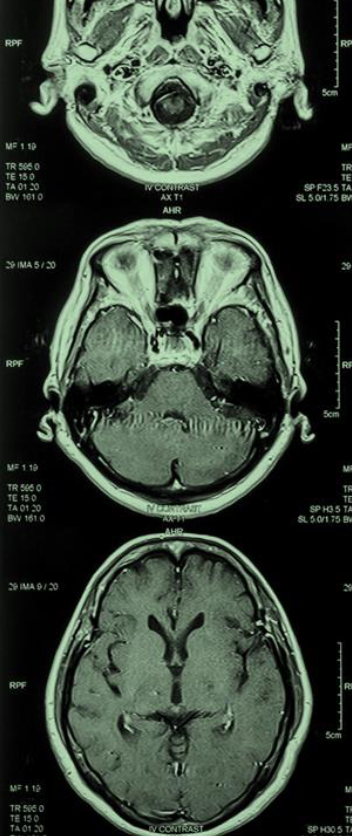

The field of Alzheimer’s disease (AD) research and treatment seems better primed than ever to deliver new therapies with the potential to transform care. The FDA’s approval of aducanumab in June 2021, though contentious, marks the first authorization of a therapy that targets the fundamental pathophysiology of the disease. More than 100 disease-modifying therapies are now in clinical trials–nearly 20 of which are in phase 3.3 The identification of biomarkers for AD has created new avenues for scientific exploration and increased hope that AD will one day be a treatable condition.

More than 6.5 million Americans are living with AD – a number projected to more than double by 2050 as the population ages. Without treatment, affected individuals face a progressive and ultimately lethal neurodegenerative disorder that destroys memory and thinking skills necessary to carry out simple daily tasks. As case numbers rise, healthcare and other societal costs associated with AD are predicted to reach $1.1 trillion.